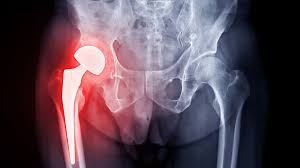

Introduction Hip pain and stiffness can significantly affect mobility and quality of life. Conditions such as osteoarthritis, rheumatoid arthritis, hip fractures, and degenerative joint diseases often lead to chronic...

Introduction Chronic hip pain can make even the simplest activities like walking, sitting, or bending extremely difficult. Over time, conditions such as arthritis or joint damage can severely impact...